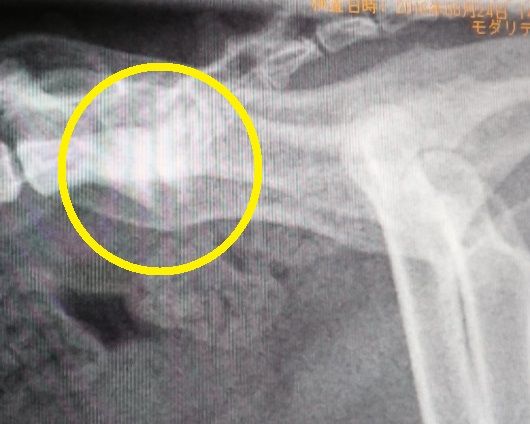

2014年:9際のレントゲン

背骨と尻尾の付け根の骨の状態の経過を年を追って見てみると、若い頃は、骨と骨の隙間もしっかり開いてましたが、2015年のレントゲンでは、先ずは、隙間がかなり狭くなって来ており、更に、2016年のレントゲンでは、骨の下の部分に突起が、これを我が家ではトケトケと呼んでいます。